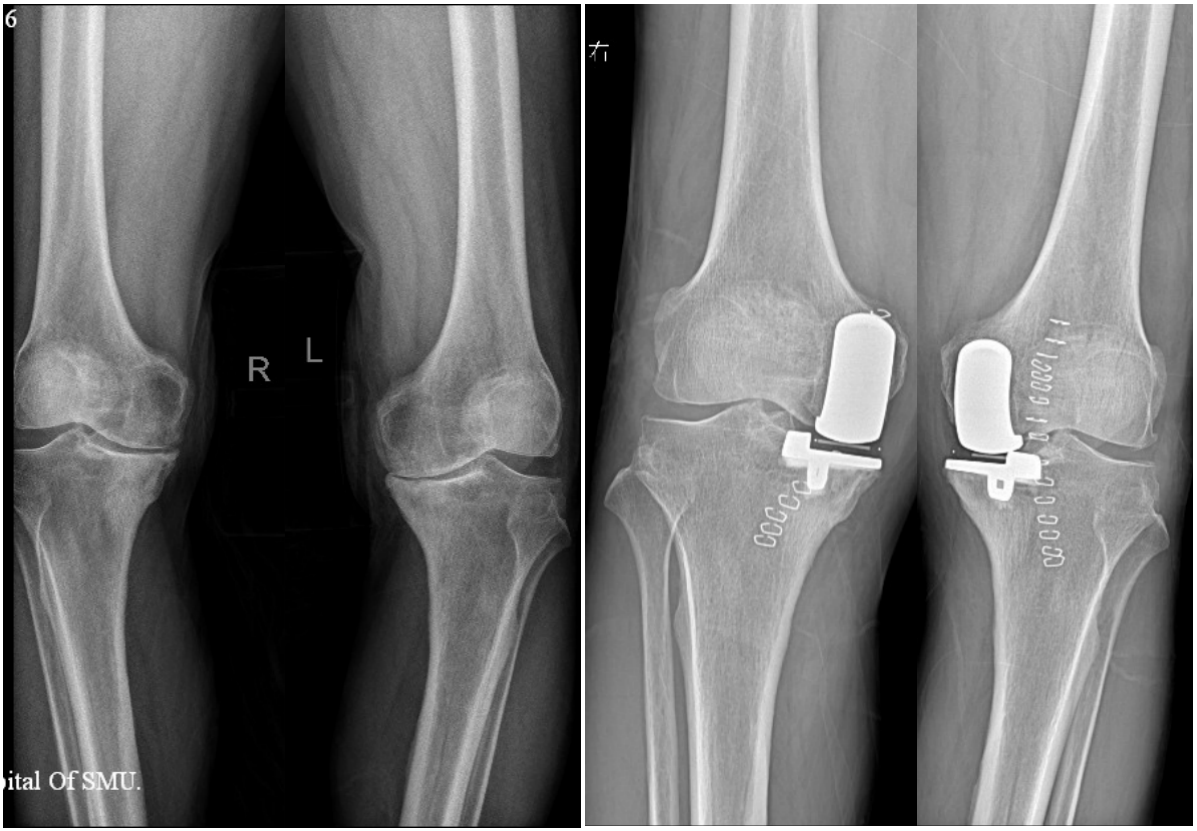

膝关节单髁置换的术前和术后X片,手术范围仅限于膝关节内侧间室

纳入标准: 1、局限于内侧间室的骨性关节炎; 2、存在完整的交叉韧带及功能正常; 3、膝关节活动度>90°,屈曲挛缩<10°; 4、内翻畸形<15°并可被动矫正; 5、疼痛局限于膝关节内侧,可用一个手指定位。

排除标准: 1、既往胫骨高位截骨手术史; 2、创伤性关节炎、痛风性关节炎、类风湿性关节炎、结核性关节炎病史; 3、严重的髌股关节炎、髌骨半脱位; 4、BMI(体重身高指数)≥26。